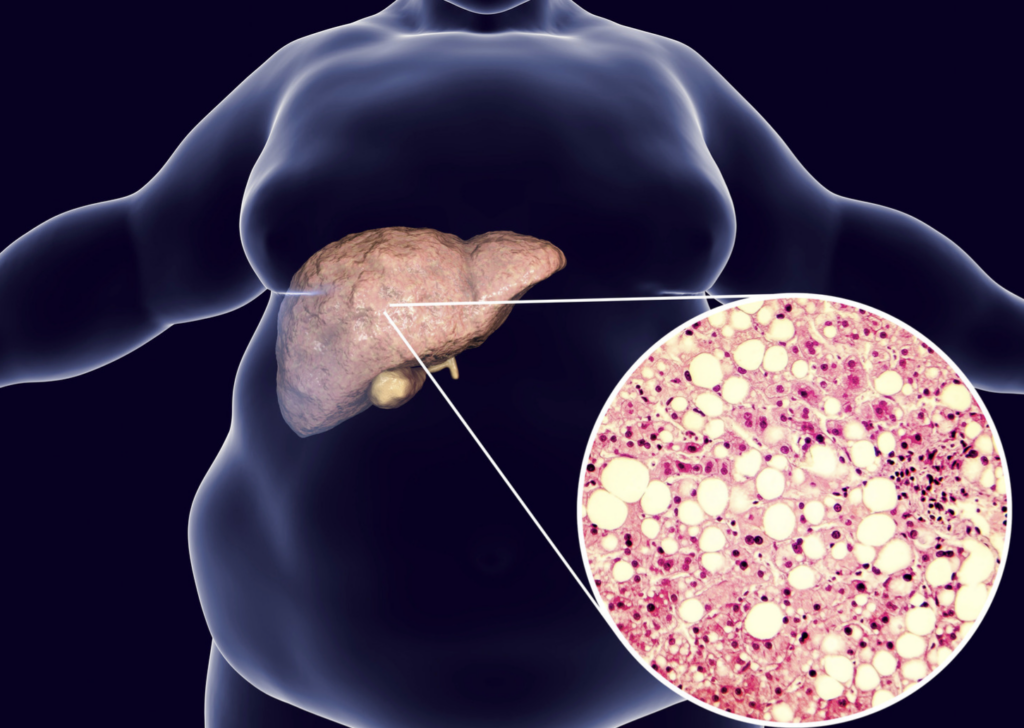

Fatty liver atau dalam bahasa melayunya, hati berlemak adalah apabila terdapat terlalu banyak lemak di dalam hati seseorang dan ia adalah perkara biasa, terutamanya pada orang yang menghidap diabetes dan berat badan berlebihan.

Hati yang sihat akan mengandungi sangat sedikit atau tiada lemak.

Lemak ini kemudiannya disimpan dalam sel hati.

Apabila lemak membentuk lebih daripada 5% hingga 10% daripada jumlah berat hati anda, anda akan mempunyai hati berlemak.

Lemak tambahan dalam hati menyebabkan keradangan hati, yang akhirnya membawa kepada parut (fibrosis) hati.